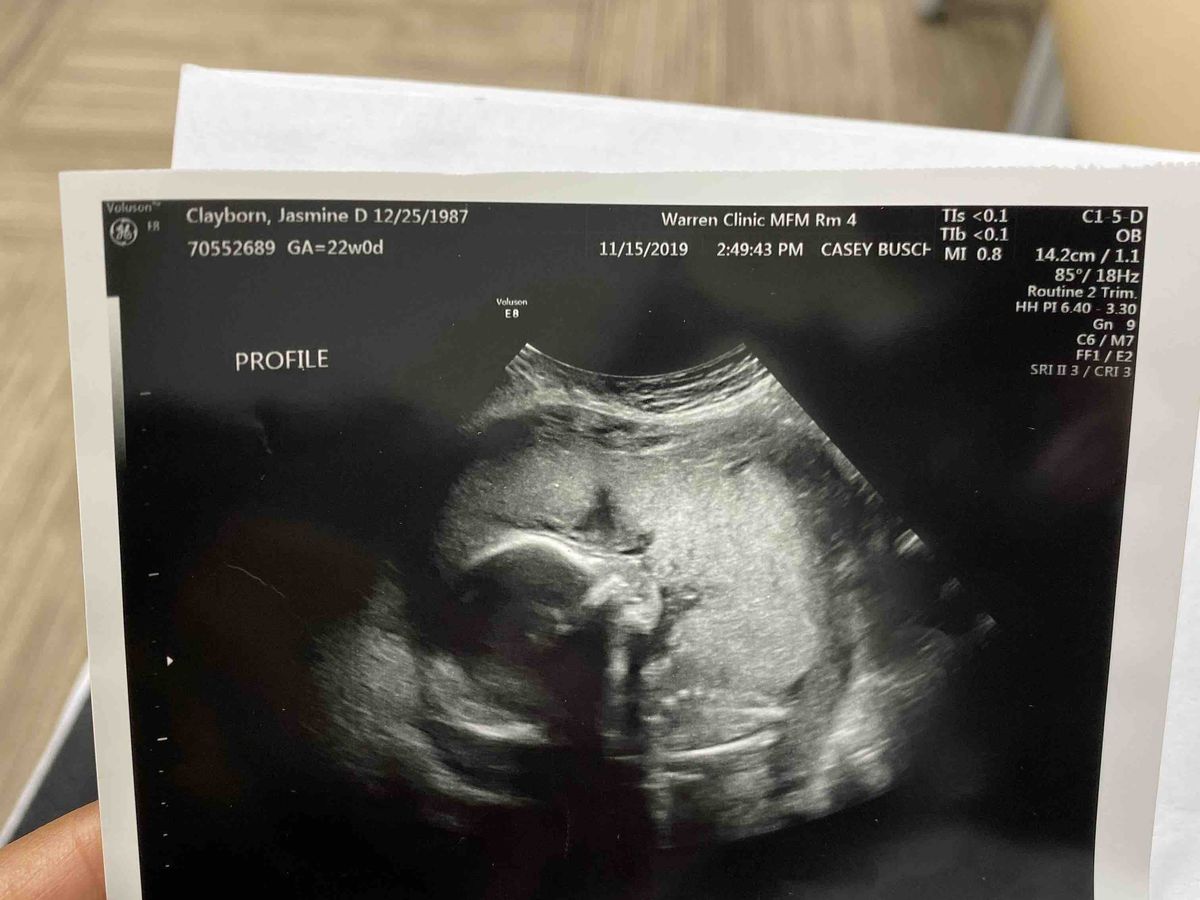

My name is Jasmine Clayborn and I’m currently 23 weeks pregnant. It hurts my heart as I write this. But every minute of everyday has become crucial to me. Recently I have found out in the worst way that my baby girl has a condition called Multicystic kidney dysplasia. Fetal multicystic dysplastic kidney (MCDK) is a condition that results from the malformation of the kidney during fetal development. The kidney consists of irregular cysts of varying sizes that resemble a bunch of grapes. It has no function, and nothing can be done to save this kidney. This defect generally only affects one of the kidneys, so typically the other healthy kidney will grow larger to compensate for the diseased one. Occasionally the disease affects both kidneys, which is incompatible with life, causing the fetus to be stillborn or to die shortly after birth. In approximately 50% of babies diagnosed with this disease, other urological defects are found. However, the other defects can generally be corrected with surgery or by observation alone. But the doctors in Oklahoma have given my daughter a death sentence despite the many alternatives that can be done to save her. They want me to carry her to 37 weeks and give birth without any intervention to save her life. Stand by and watch her take her last breath. As a mother can and will not allow that to happen. I have found a care team in Chicago that is willing to help my baby stay alive but I have to move there with in the next month or so she can be monitored and they can take the proper precautions after she is born.Im asking for any little bit to help me take the steps to save my baby. Please help me prepare for a birth and not a funeral